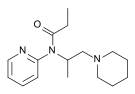

Ampromides

Structures

| Ampromides | ||||

|---|---|---|---|---|

|

|

| ||